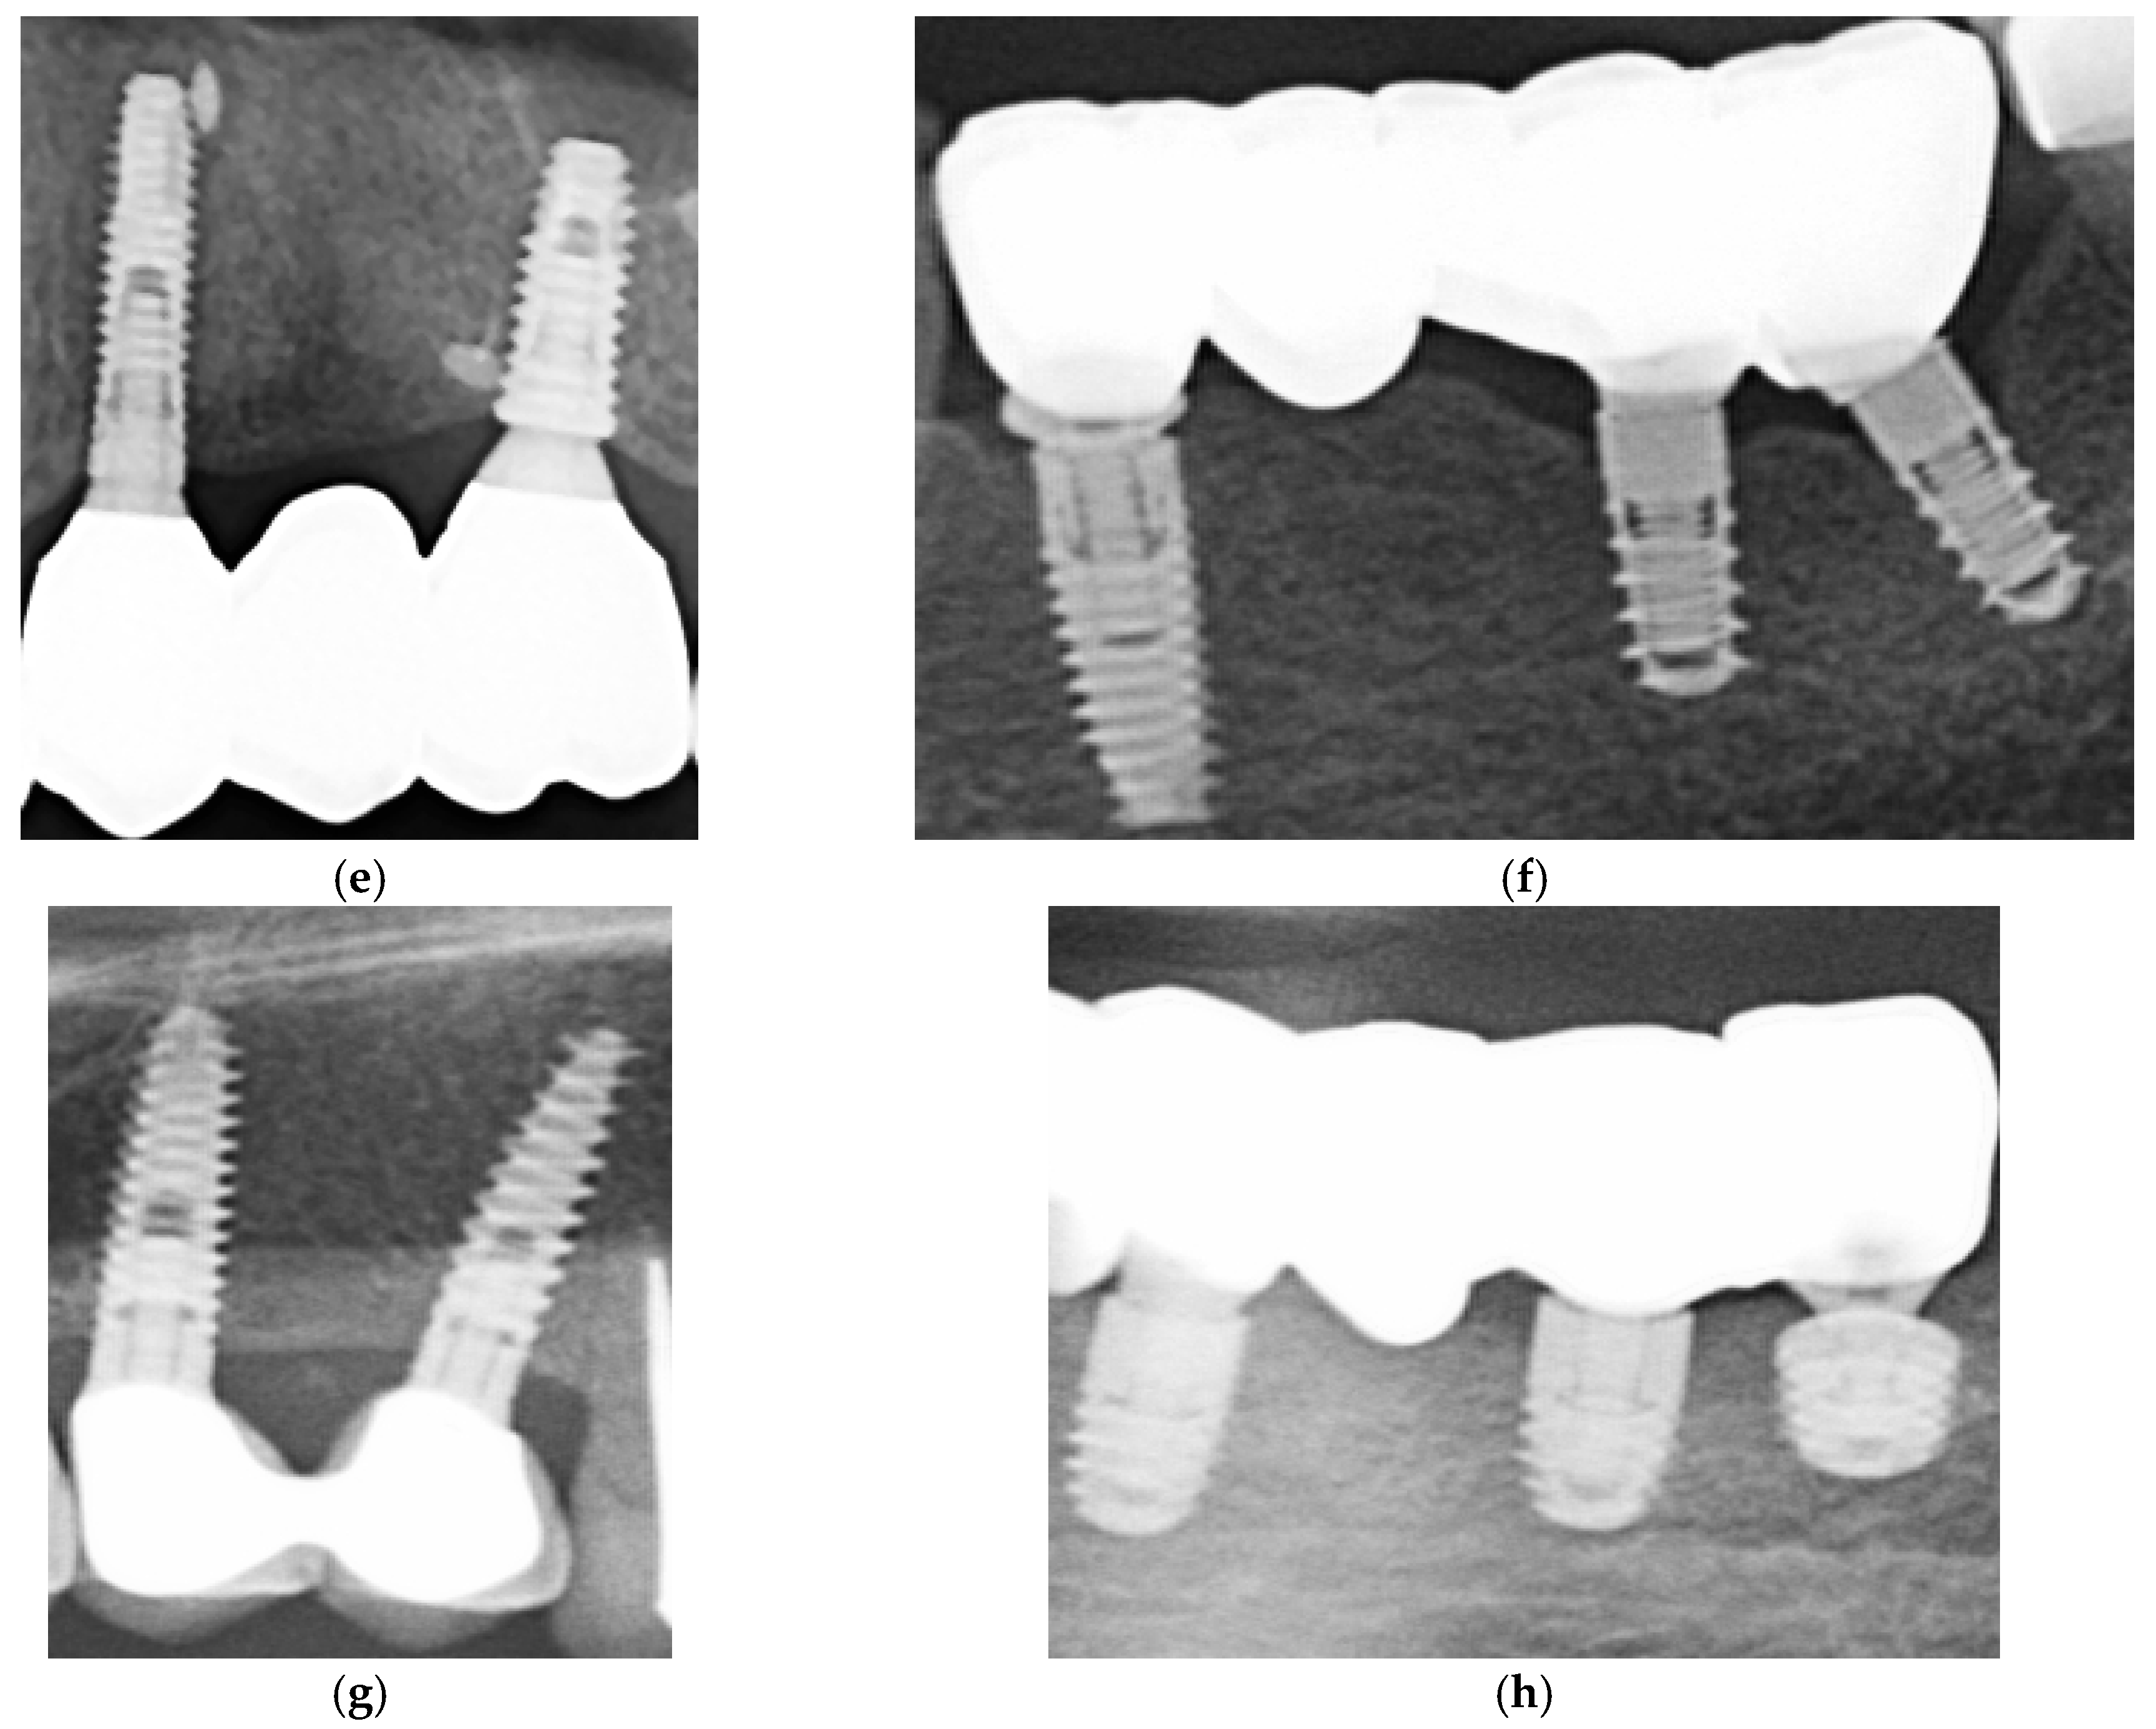

3.4. Marginal Adaptation Evaluation

Marginal adaptation was initially assessed for all cases using conventional two-dimensional (2D) periapical and panoramic radiographs (Figure 7). Due to the intrinsic resolution limitations of these imaging modalities—approximately 150 μm for panoramic imaging and 75 μm for CBCT scans—precise quantitative measurements of marginal gaps could not be reliably performed using radiographs alone. No gross misfits, open margins, or overhanging contours were detected in any of the reviewed images, and all restorations were classified as radiographically acceptable, without apparent marginal discrepancies linked to early failure or peri-implant inflammation.

To supplement the radiographic evaluation, a subset of clinical images was analyzed using ImageJ software (Fiji version) to obtain semi-quantitative estimates of marginal gaps. Radiographic images were imported into ImageJ (NIH, Bethesda, MD, USA) for marginal-gap evaluation. Each image was calibrated to real dimensions using a visible reference, such as the known abutment diameter. The pixel-to-mm scale was set in ImageJ using this known reference dimension visible in each image. For each restoration, three points were selected along the visible crown–abutment interface within the 2D radiographic projection (typically near the mesial, central, and distal regions of the imaged side). Linear measurements were taken perpendicular to the interface at these locations to estimate the apparent gap width. Each time, three measurements were performed, and mean values were calculated after verifying consistency. The results were interpreted as qualitative indicators of marginal adaptation, suitable for comparative analysis between groups rather than absolute measurements. These ImageJ-derived values were interpreted strictly as semi-quantitative approximations, not true marginal-gap measurements, due to the intrinsic resolution limitations of 2D radiography.

Although these measurements were constrained by image resolution and calibration, they suggested a trend toward smaller marginal discrepancies in restorations cemented with Fuji Plus® compared to those cemented with DentoTemp™. Representative radiographic examples from the study are presented in Figure 8.

Figure 8. Sections of OPGs from study cases. The left panels (a,c,e,g) show restorations cemented with Fuji Plus®, while the right panels (b,d,f,h) show restorations cemented with DentoTemp™. Images illustrate representative follow-up cases used for radiographic evaluation of retention and marginal adaptation.